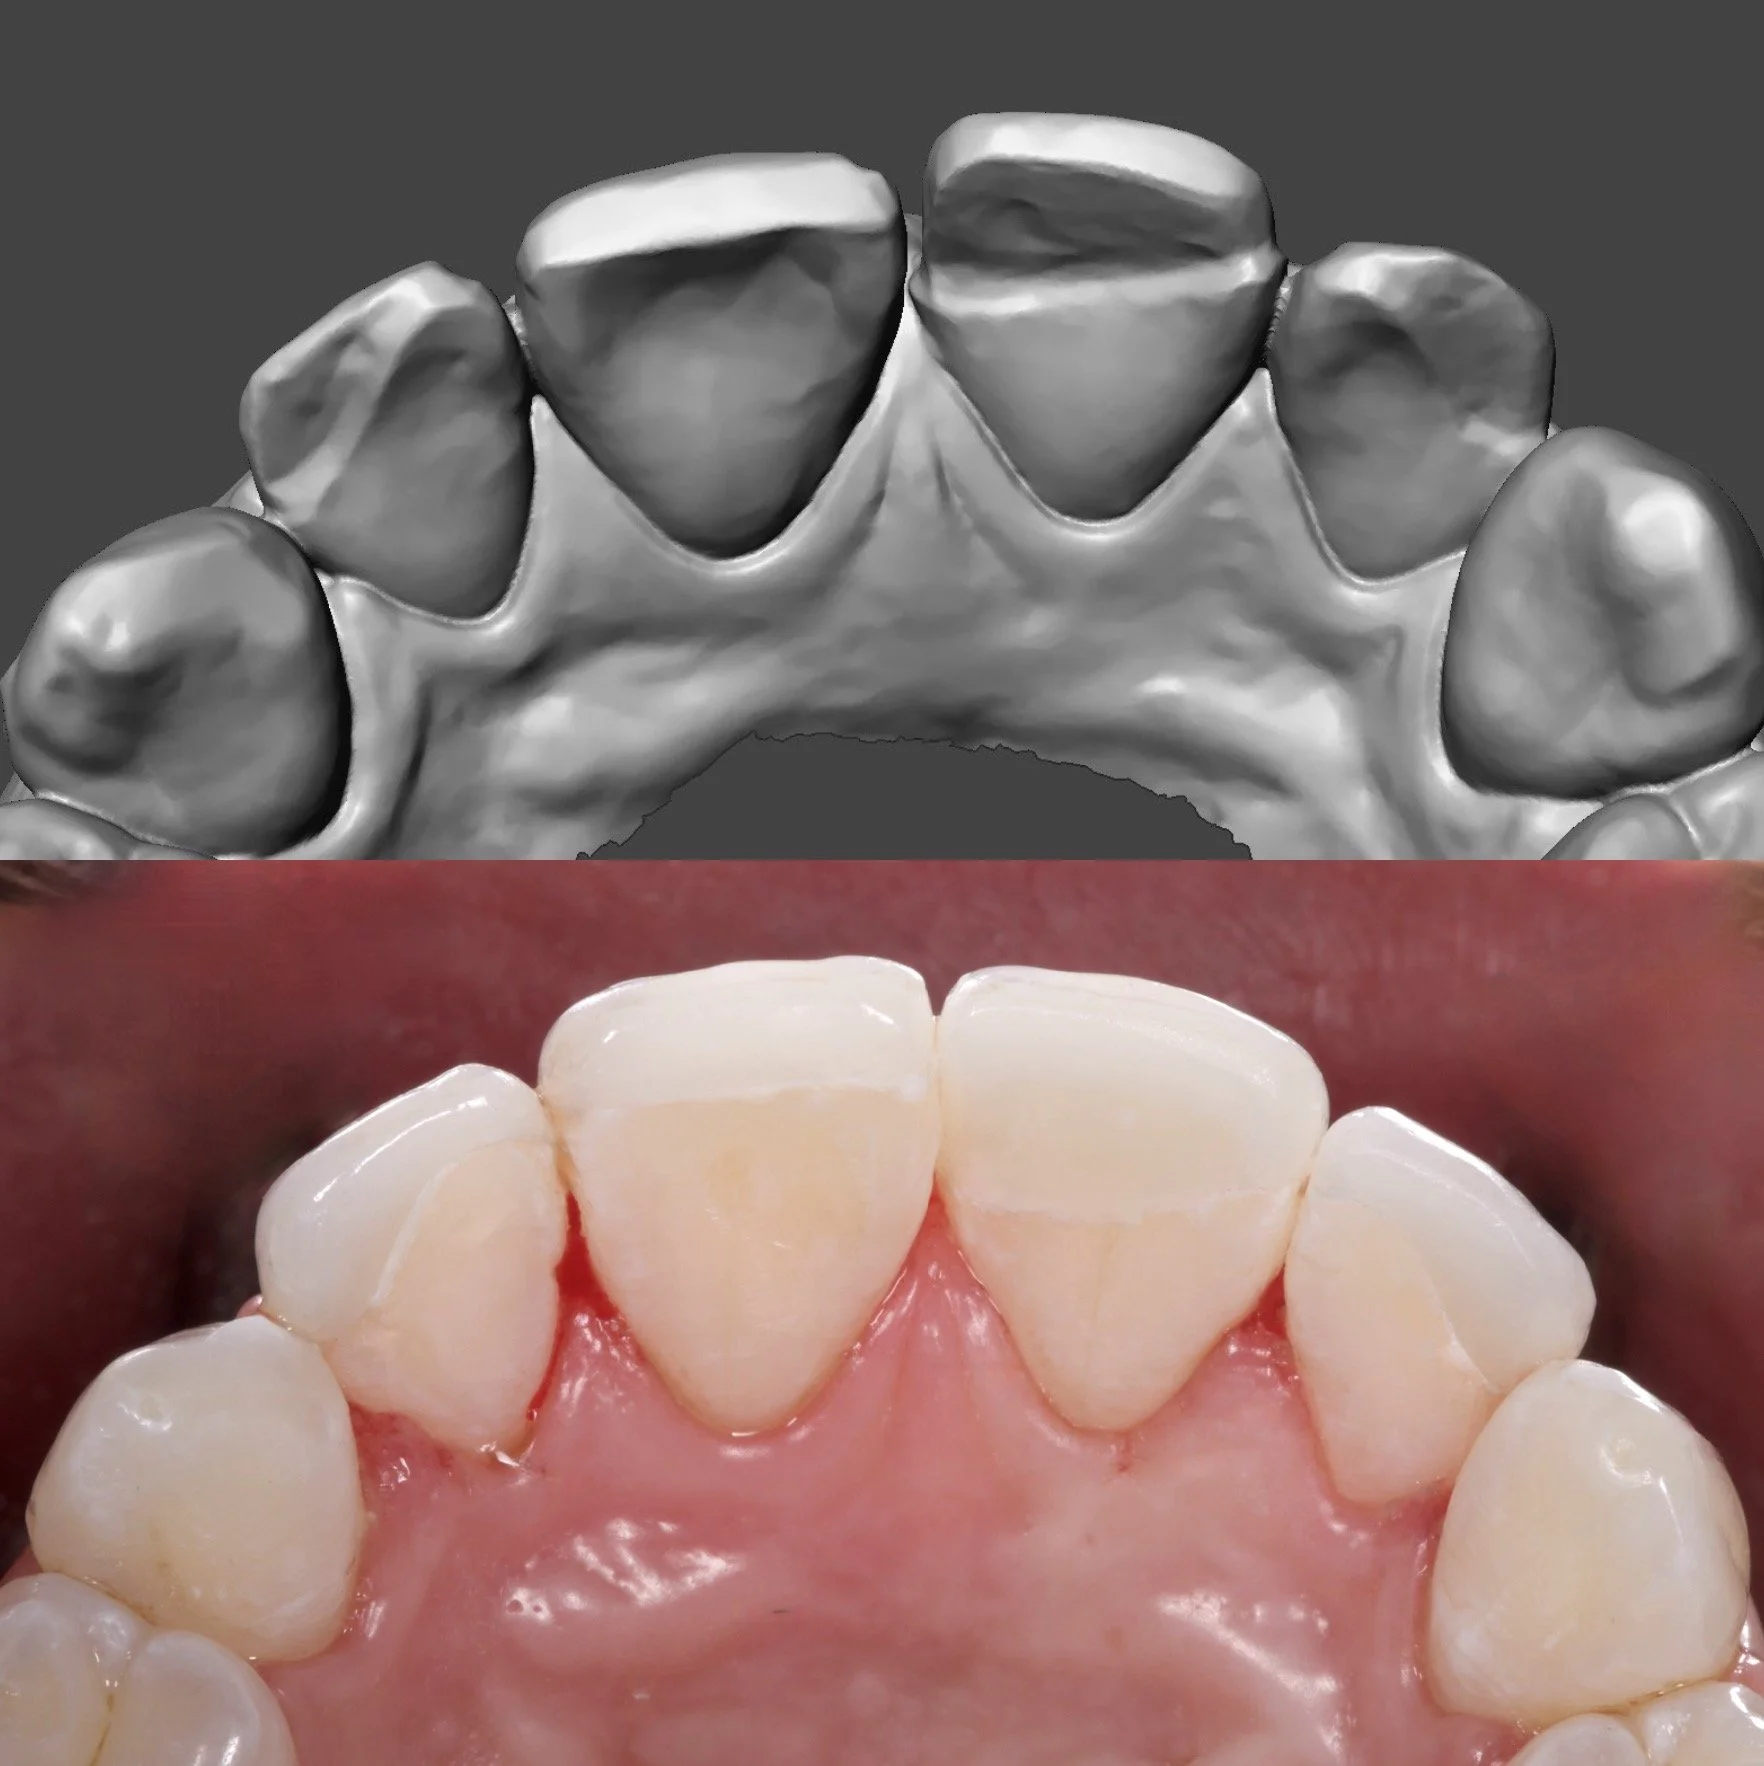

4 Minimal Prep Veneers in Shade 0.5M1

Dr. Heldt, 2025. Newport Beach, California.

Because the patient is not interested in orthodontics, we were able to have the teeth appear straightened with 4 veneers. This is not the doctor’s recommendation by the way. 4 Layered eMax Veneers (#7-10) in Shade 0.5M1. Diagnostic waxup with patient-approved temporaries for shape and shade. Low translucency. No staining.